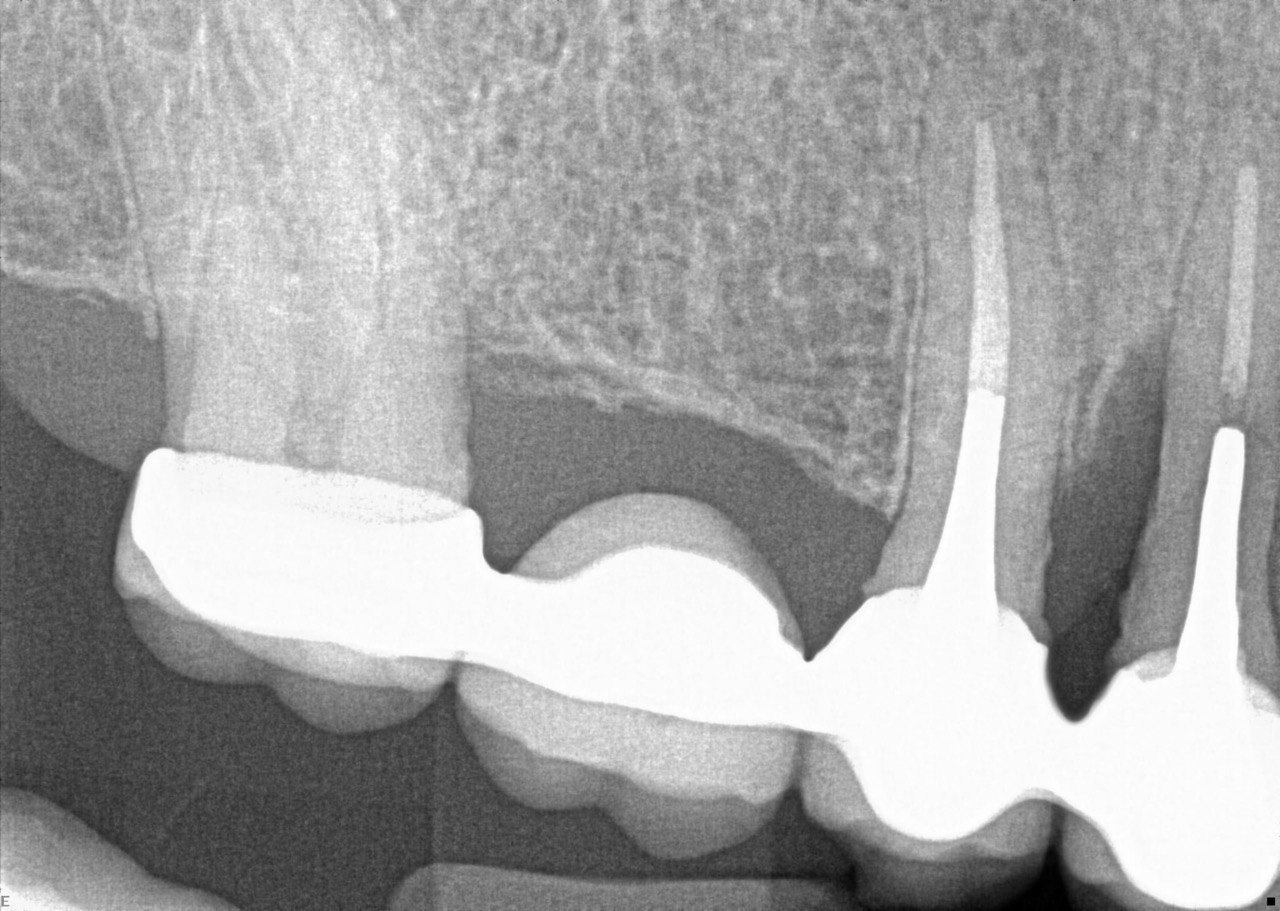

Question 11: Which materials cannot be seen in the print of the X ray?

Question 12: What option cannot be selected for the following X ray?

Question 13: What option cannot be selected for the following X ray?

Question 14: Which surface shows overhang restoration?

Question 15: Which surface shows overhang in the restoration?

Question 16: Which surface shows overhang?

Question 17: Which surface shows overhang?

Question 18: Which surface shows overhang?

Question 19: Which option can be chosen for the tooth # 3.6?

Question 20: which tooth shows defective resotration?